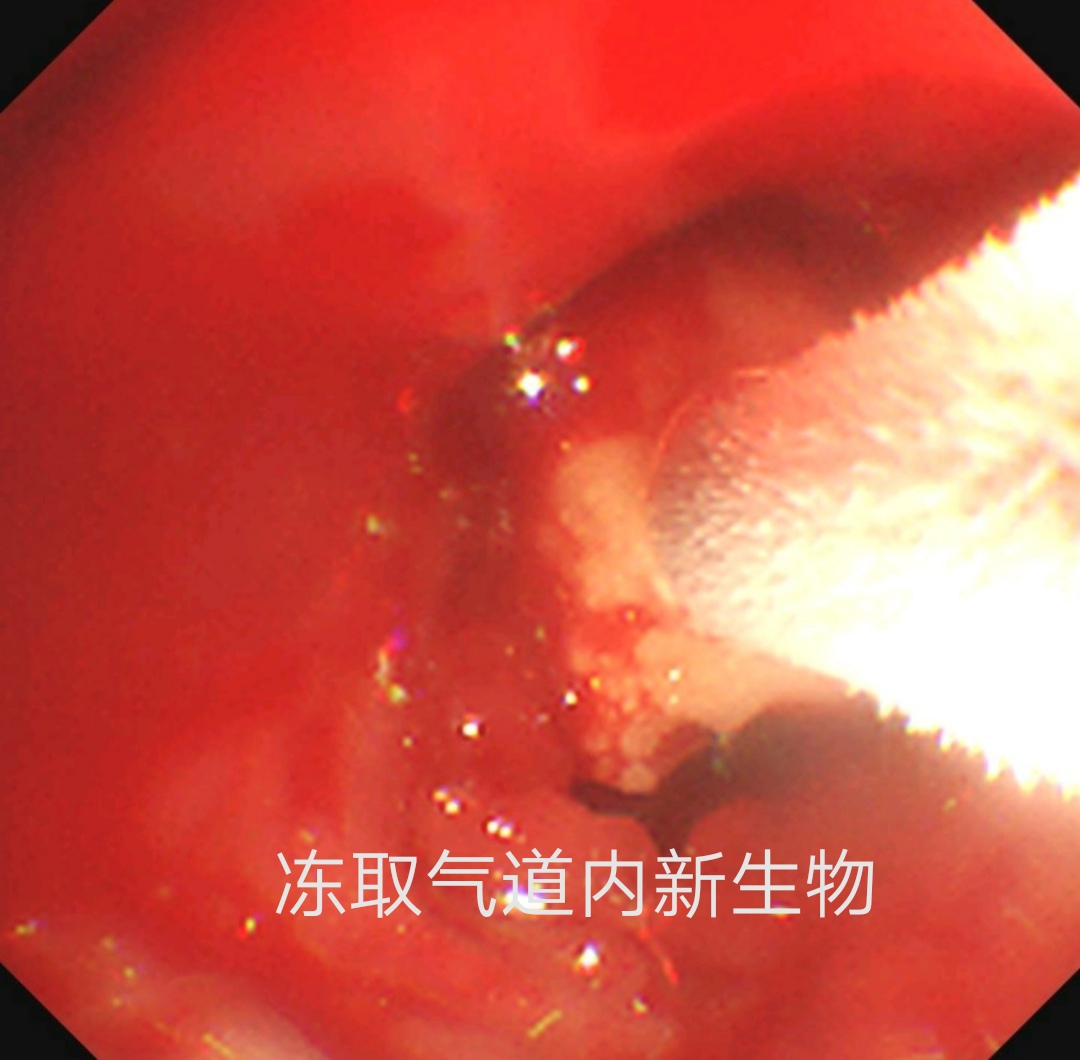

经专家再次会诊,决定进行第二次支气管镜检查并清除气道内新生物,为了保证手术安全性和效果,检查时采用了全麻硬质气管镜和可弯曲支气管镜结合的手术方式,成功冷冻取出支气管病变,发现竟是被坏死物包裹的半块花生米。